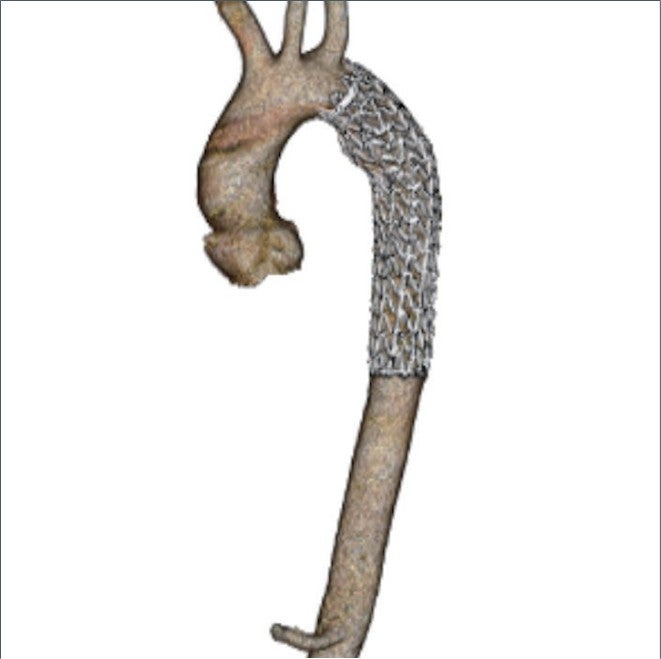

術前のサイジングで中枢ランディング径は25 mmであり、左鎖骨下動脈から大動脈損傷部までのランディング長は小弯側の測定で18 mmであった。外傷により損傷されている部位の長軸方向の長さは40 mm程度であるが、その遠位の下行大動脈は壁内血腫様の所見であった。遠位ランディング径は21-23 mmであり、ステントグラフトは28 mm-15 cmを使用することとした。

輸血で血圧を維持しつつ全身麻酔にて右鼠径部を切開し総大腿動脈を露出した。ヘパリンを投与したのち8 Frのシースを挿入、ここから注意深くピッグテールカテーテルと血管造影用ガイドワイヤーを上行大動脈まで挿入し、スティッフガイドワイヤーに入れ替えたのち、シースをゴア®ドライシール フレックス イントロデューサシース20 Frに入れ替えた。TAG®コンフォーマブル ステントグラフト アクティブコントロールシステムTGM282815Jを弓部大動脈まで挿入、造影用pigtailカテーテルを上行大動脈まで挿入ののち、LAO45度にてDSAを撮影し、左鎖骨下動脈および大動脈損傷部の位置関係を確認し、マーキングした。ステントグラフトの展開はスティッフガイドワイヤーにて大弯にステントグラフトを押し付けた状態で、中枢端のパーシャルアンカバードステントがわずかに左鎖骨下動脈にかかる程度に固定し展開した。最後にangulation controlを使用し小弯側を十分に圧着させて展開終了とした。DSAにて明らかなエンドリークのないことを確認した。また、展開後は不安定であった血圧も安定した。デリバリーシステムを回収し、右総大腿動脈を修復し、プロタミン投与ののち閉創した。手術時間は58分であり、当院搬入からステント挿入まで約130分であった。

TAG®コンフォーマブル ステントグラフト アクティブコントロールシステムは外傷に対して適応となる唯一のデバイス*であり、構造的に比較的短い中枢ランディングでもシーリング効果を発揮するよう設計されている。更に、本症例ではangulation controlを用いることにより弓部小弯側の大動脈壁にステントグラフトを密着させることができ、エンドリークは生じなかった。外傷性大動脈損傷症例は中枢ランディングが短く、弓部の角度が急峻であることが多いため、小弯側ランディングが問題になるが、アクティブコントロールシステムにより従来以上にエンドリークを抑制するための機能が追加されたことで、外傷性大動脈損傷に対して更に効果を発揮できることとなったと言える。